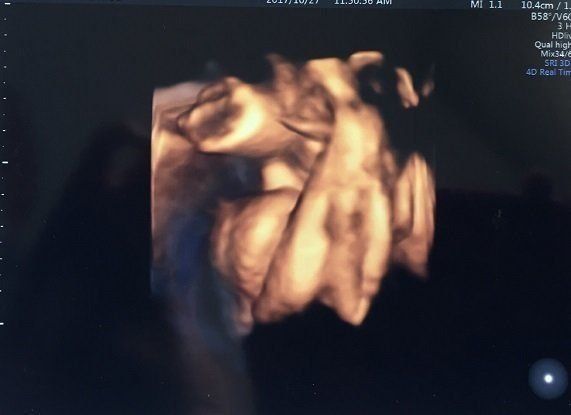

セイコさんの妊娠34週目のエコー写真 里帰り出産のため実家の産院へ移る

こちらの産院だと毎回4Dが撮ってもらえるので、楽しみです。かわいらしい手が結構はっきり写っています。手もほっぺもだいぶぷっくり?体重は2160g、頭の大きさは8.5㎝だそうです。